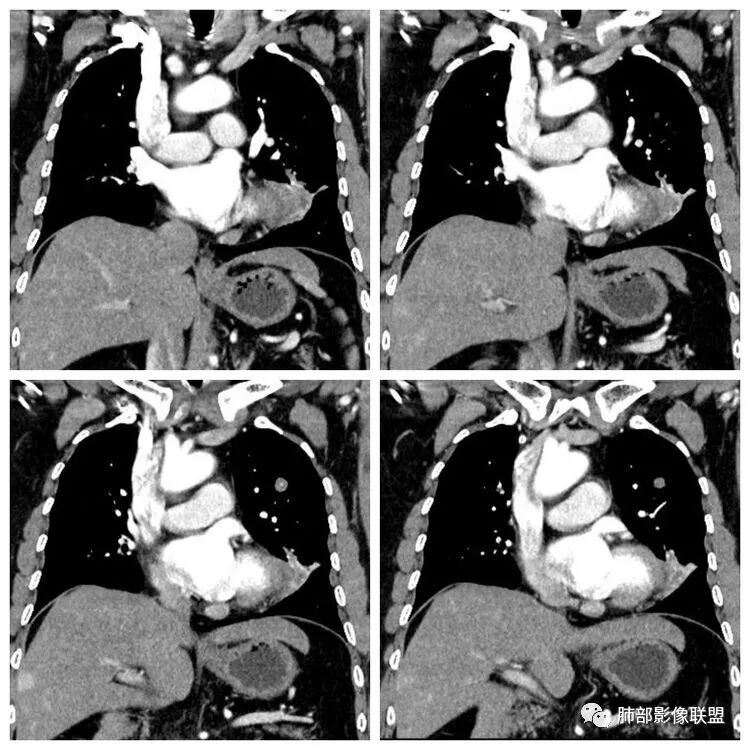

平扫 动脉期 静脉期  40HU、48HU、57HU

患者老年男性,“左肺占位”收入住院。查CEA轻度升高。胸部CT:左肺肺门占位并左肺下叶阻塞性,远端肺组织膨胀不全,增强可见轻度强化,内似见低密度灶。双肺多发类圆形结节,以左肺上叶尖后段为大,内可见部分钙化,边缘光滑、清楚。综合考虑恶性病变,鳞癌并转移可能大,鉴别腺癌、结核。

胸CT:左下叶内前基底段肿块,支气管堵塞,强化弱,延迟强化,两肺多处结节,右上肺门淋巴结大。常规考虑:肺癌可能 ,肺内小结节,转移?鉴别:错构瘤,TB等。

左肺下叶占位,左肺下叶前内支气管阻塞可疑(缺乏薄层),病灶有膨胀性,远端较内侧细,增强病灶强化不明显——乏血供病灶,病灶沿支气管生长,考虑恶性病变,左肺上叶可见小结节病灶,边缘光滑清晰,考虑转移瘤,综上所述考虑恶性病变,左肺下叶小细胞类癌可能,左肺上叶转移。

左肺下叶结节支气管进入截断,远端肺不张,增强后坏死不均匀,肺癌明显,至于病理类型,鳞癌,小细胞,腺癌都有支持和不支持的地方,个人倾向于鳞癌可能,理由,纵隔淋巴结肿大不明显,远端阻塞性不张,支持小细胞的地方,坏死呈沼泽样,但纵隔无明显淋巴结肿大及冰冻表现。腺癌这种表现一般为低分化腺癌,但远端阻塞性不张及纵隔无明显淋巴结肿大不支持。

4.增强扫描左肺门区块影轻度强化,强化程度轻于舌段周围不张肺组织。

6.分析:男性患者,左肺门区块状影,支气管阻塞,强化不显著,未见淋巴结肿大,更多见于肺鳞癌。难以解释的是下肺病灶的生长方式。

沿肺门或是叶裂缺损孤立发生且蔓延,转移性腺癌似乎可以解释,但占据较大支气管腔就属罕见了。